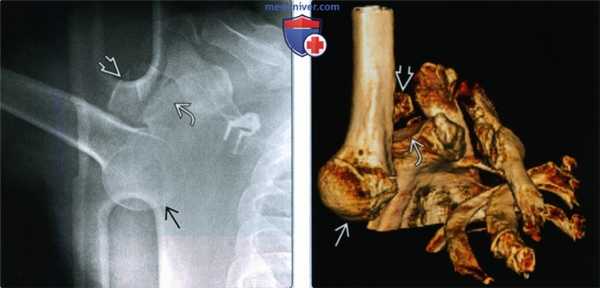

(Слева) Осевая КТ, пациент с ранее вправленным вывихом, которого сейчас беспокоит передняя нестабильность и боль. Имеется перелом Банкарта переднего края суставной впадины КТ позволяет оценить перелом Банкарта, который не виден на рентгенограмме и помогает при дооперационном планировании.

(Справа) На передне-задней 3D КТ у этого же пациента определяется перелом Банкарта передненижнего края суставной впадины. У пациента также имеется небольшой вдавленный перелом Хилла-Сакса заднелатеральной верхней области головки плечевой кости.

3. КТ при переднем вывихе плеча:

• После вправления: более чувствительная при демонстрации переломов Хилла-Сакса и Банкарта, чем рентгенография:

о При большом переломе Хилла-Сакса и рецидивирующем вывихе: помогает планировать операцию с костным трансплантатом

о Потеря участка кости суставной впадины или большой перелом Банкарта: помогает планировать вмешательство Бристоу-Латарьета